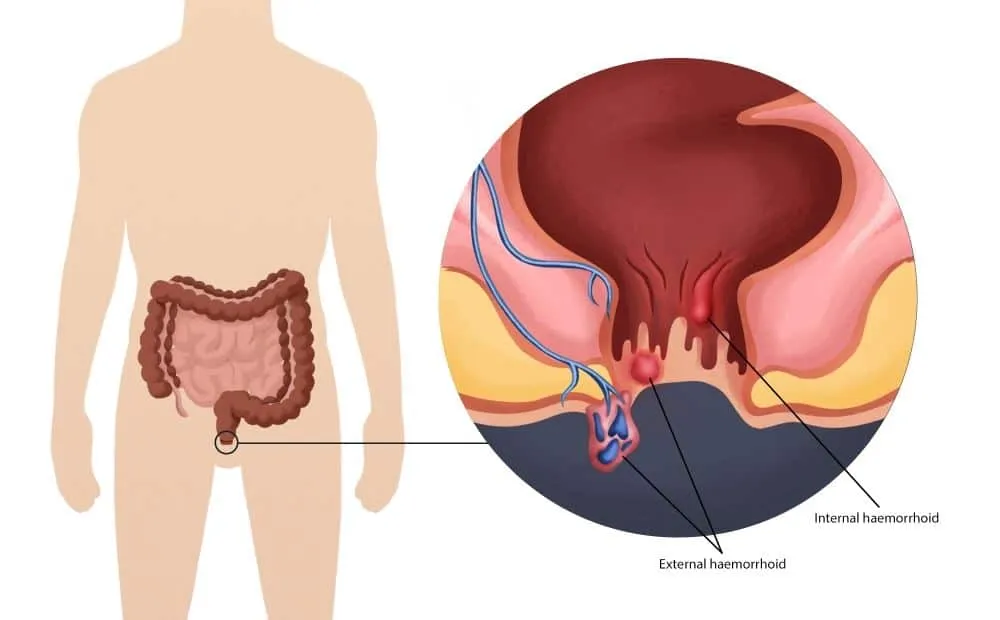

Seeing blood during passing stool can be frightening. While many people ignore it or delay talking to a doctor due to embarrassment, rectal bleeding should never be ignored.